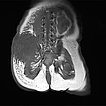

Native T1-weighted MRI shows the tumor to be hypointense. The tumor has blurred margins. The surrounding adipose tissue is saturated with lymphedema.

In corresponding T2-weighted, fat-saturated MRI, the tumor shows hypointense parts (hemorrhages), but also hyperintense parts and is overall very inhomogeneous and blurred. The surrounding fat tissue is saturated with lymphedema.

This surrounding subcutaneous lymphedema (hyperintense in axial T2-weighted, fat-saturated MRI ) is a typical feature of kaposiform hemangioendothelioma and also extends significantly in the surrounding area.